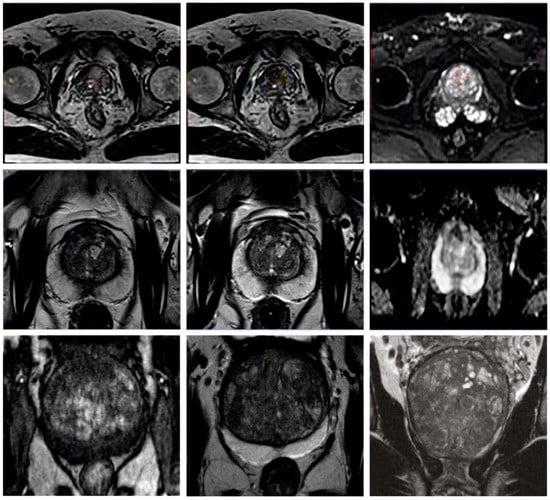

The proposed model was simulated using the Python 3.6.5 tool on a PC configured with the following specifications: i5-8600k, GeForce 1050Ti 4GB, 16GB RAM, 250GB SSD, and 1TB HDD. The parameter settings are learning rate: 0.01, dropout: 0.5, batch size: 5, epoch count: 50, and activation: ReLU. The current section discusses the PCa classification results achieved by the proposed AOADLB-P2C model. The model was tested on a dataset comprising 400 samples under two classes, as defined in Table 1. Figure 3 depicts some of the sample images used in this study.

Figure 3.

Sample images.